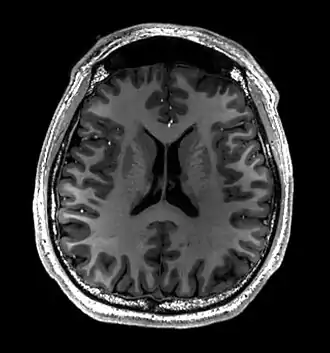

Brain regions on T1 MRI -

T1 (note CSF is dark) with contrast (arrow pointing to meningioma of the falx) -